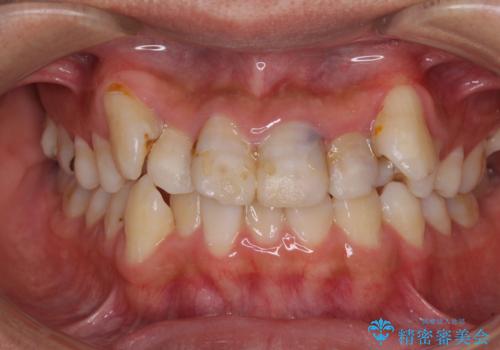

デコボコと変色した前歯 抜歯矯正と審美歯科治療

- 八重歯と上顎前歯の変色を気にして来院された患者様です。

上下ともに八重歯が顕著であったため、上下左右の第一小臼歯4本を抜歯し、ワイヤー装置での抜歯矯正を行うこととしました。

前歯は根管治療が必要な歯を事前に根管治療を行い、矯正治療後にオールセラミッククラウンにて補綴治療を行うこととしました。